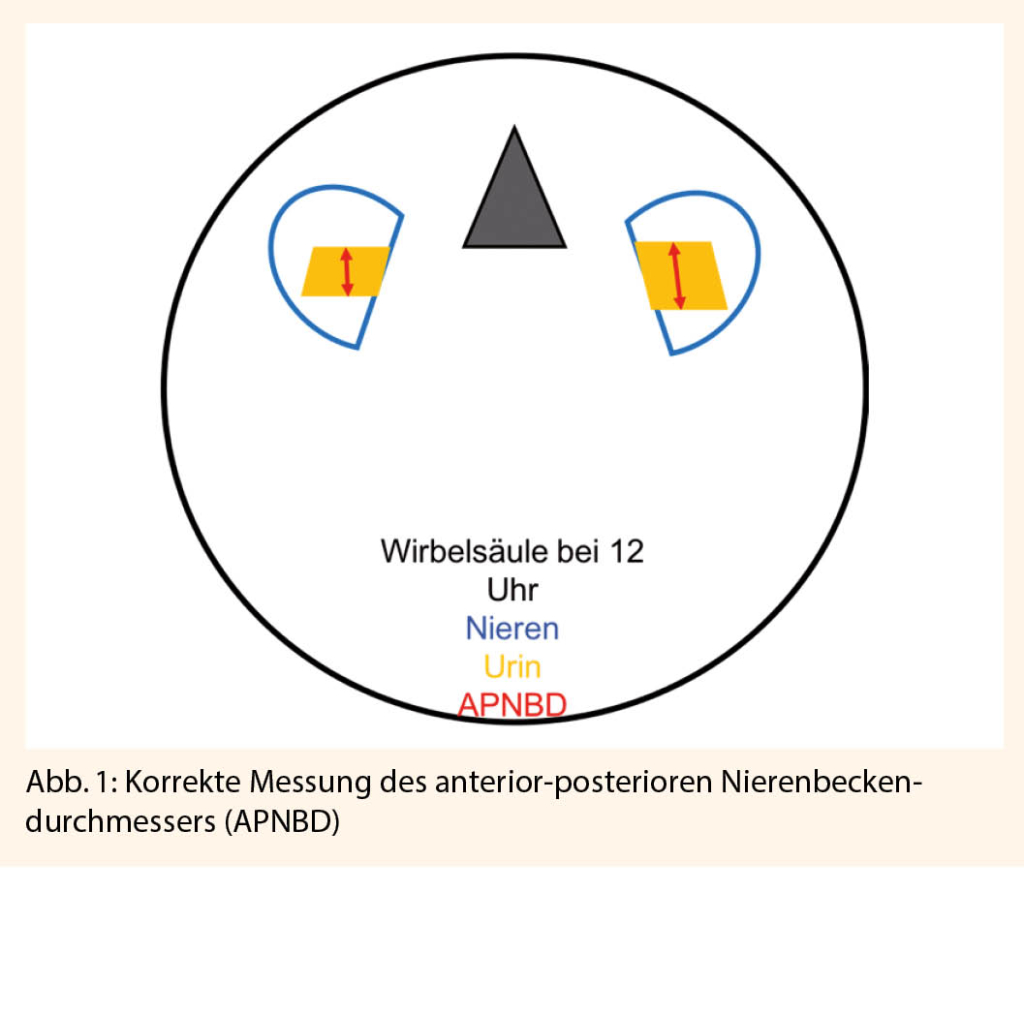

Pränatal wird primär meist der anterior-posteriore Nierenbeckendurchmesser (APNBD) angewendet, um die renale Flüssigkeitsansammlung quantitativ zu beschreiben. Die Messung sollte in einer transversalen Schnittebene mit der Wirbelsäule bei 6 oder 12 Uhr und von der jeweils inneren Grenze der Flüssigkeitsansammlung erfolgen.